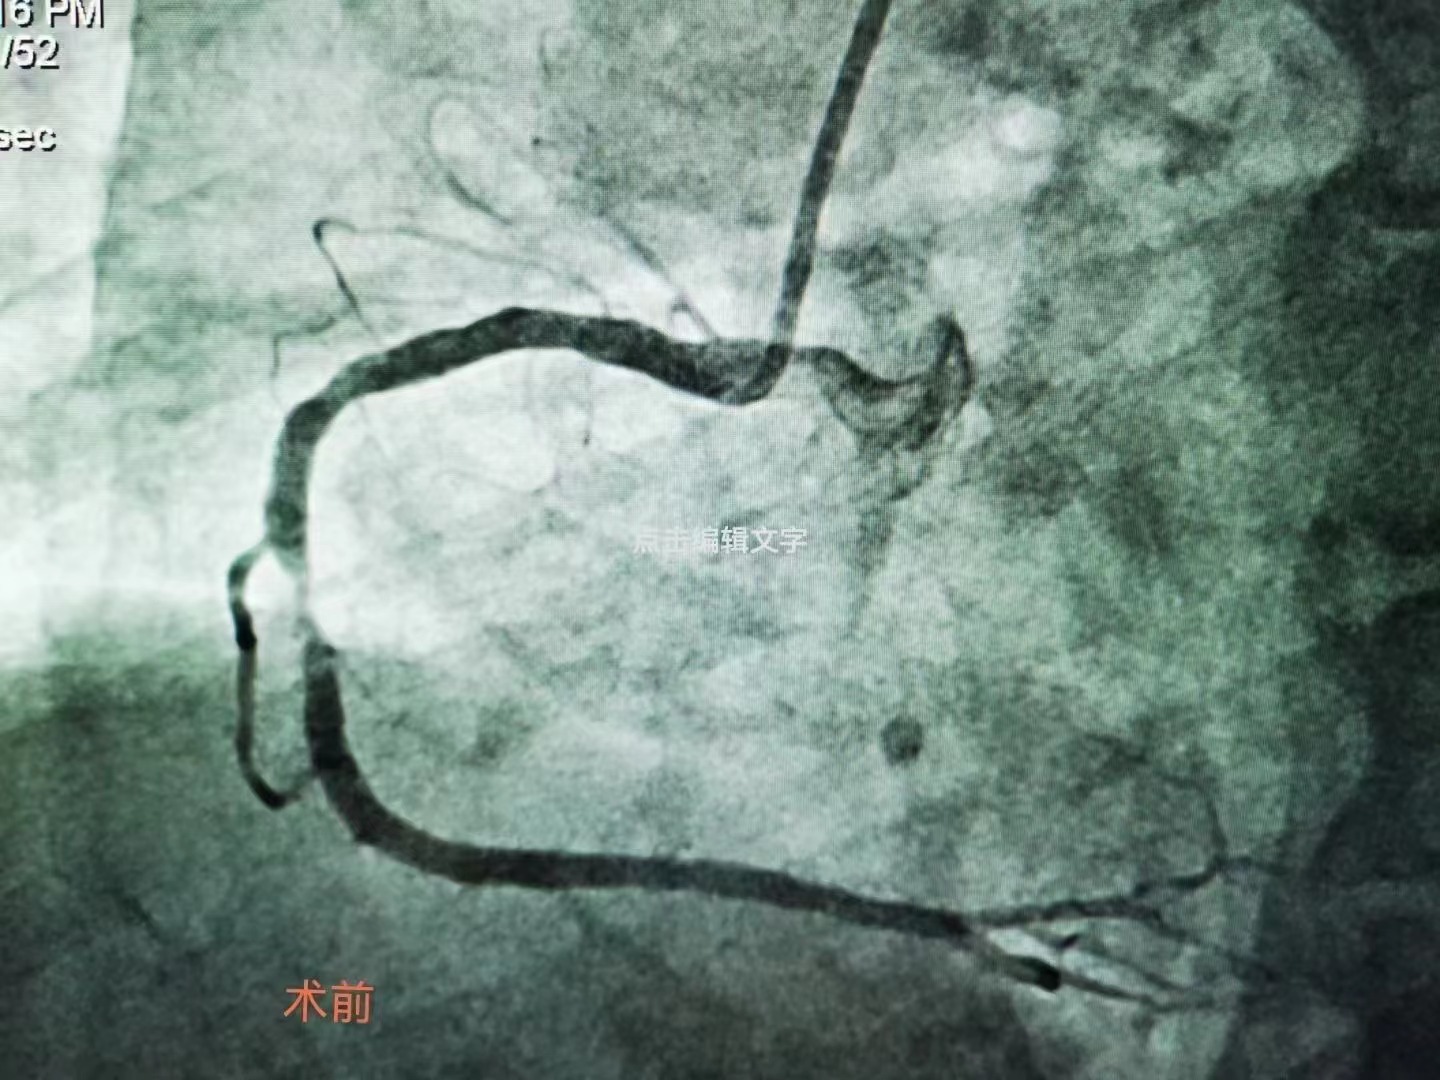

祝賀大連醫科大學附屬第二醫院醫院趙昕專家團隊成功為患者植入Xinsorb生物可吸收支架! 精準操作,完美貼壁

祝賀大連醫科大學附屬第二醫院醫院趙昕專家團隊成功為患者植入Xinsorb生物可吸收支架!

精準操作,完美貼壁